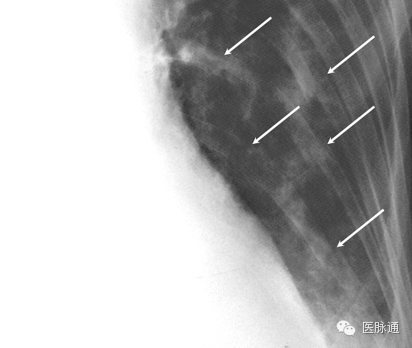

连枷胸为至少3根肋骨2处或多处骨折造成胸段的异常运动。在吸气相,由于胸腔内负压的影响,受累节段回缩。连枷胸通常见于胸部严重钝性创伤后。根据胸片评估肋骨骨折可能非常困难,并且需拍摄多角度斜位片,以及密切关注细节。图13为胸片的放大影像,显示由箭头所示肋骨骨折造成的连枷胸。若怀疑骨折但未得得到胸片确诊,可能需要进行CT扫描。

图13